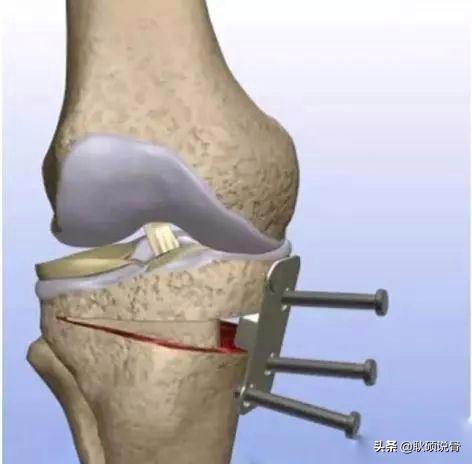

第二种,而对于较重的膝关节骨刺反复关节镜效果不佳,可以选择高位胫骨截骨(HTO)。适用于有先天性骨性内翻畸形、创伤后畸形。在纠正力线的同时,保留了所有的关节内结构。不过年龄过大,骨质疏松严重的患者不适合应用此种方式。